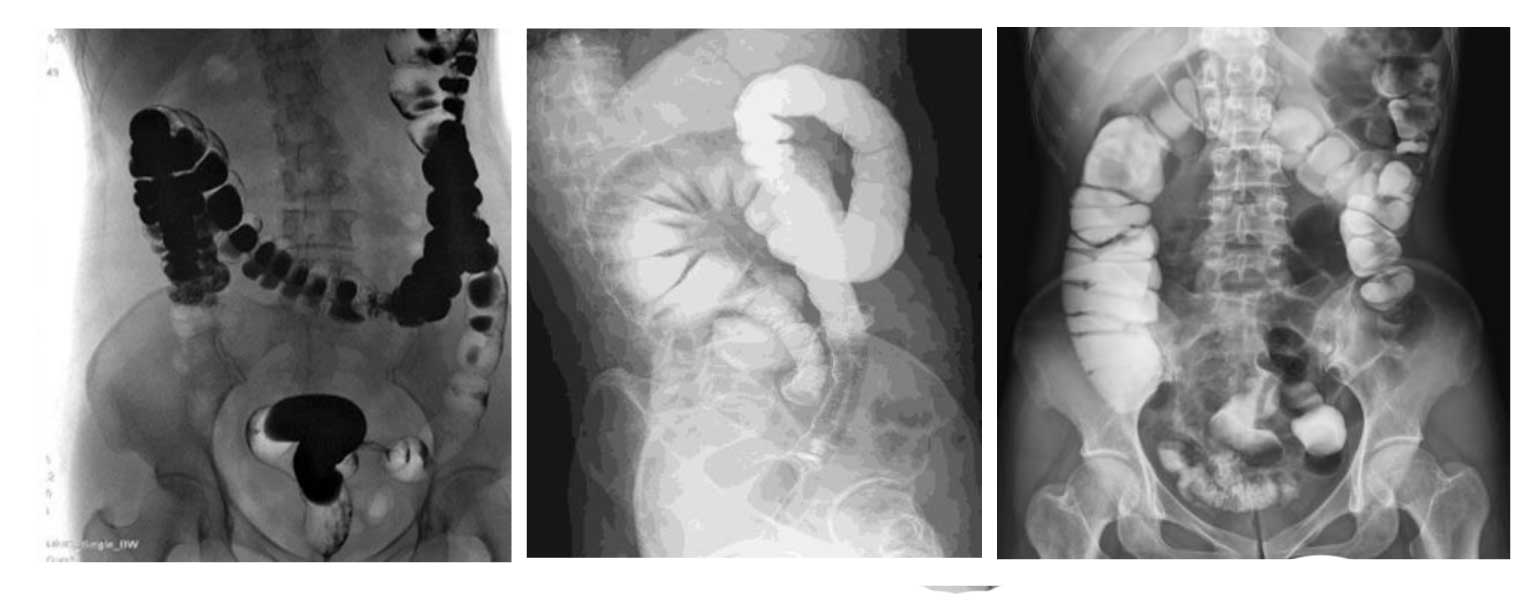

Рентгенологические исследования: рентгенография больших переломов костей и масштабное физическое рентгенографическое обследование, флюороскопия всех частей тела (грудная клетка, живот и т.п.), пищеводная ангиография, ангиография верхних отделов желудочно-кишечного тракта, полная ангиография желудочно-кишечного тракта, оральная холецистография, внутривенная холангиография, Т-образная холангиография, ЭРХПГ, внутривенная пиелография, гистеросальпингография и т.д.